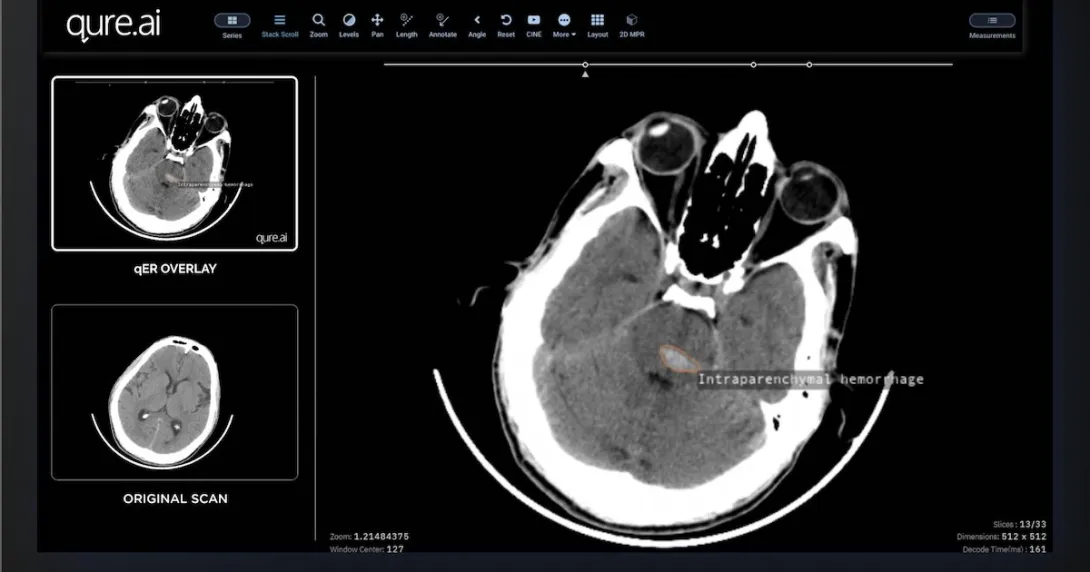

Qure.ai offers AI solutions that help streamline the stroke care pathway. One of its flagship products, qER, delivers quick reading and interpretation of heart CT scans with a turnaround time of two minutes. This information is then stored on the Qure app, a mobile platform that can connect all multidisciplinary teams from different hospitals.